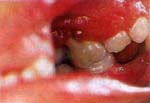

Al examen clínico se observó una pérdida severa de inserción gingival con pérdida ósea y compromiso furcal en al zona vestibular del segundo molar superior izquierdo temporal, movilidad dental asociada, dolor, gran acúmulo de placa bacteriana y libre de caries (Fig.1). En el canino inferior izquierdo temporal se observó una pérdida de inserción gingival den la zona distal y lingual sin movilidad, gran acúmulo de placa bacteriana y asintomético.

| Fig.1 Severa perdida de inserción gingival con pérdida ósea y compromiso de la furca del segundo molar izquierdo temporal en un niño de 7 años con leucemia linfoblástica aguda. |